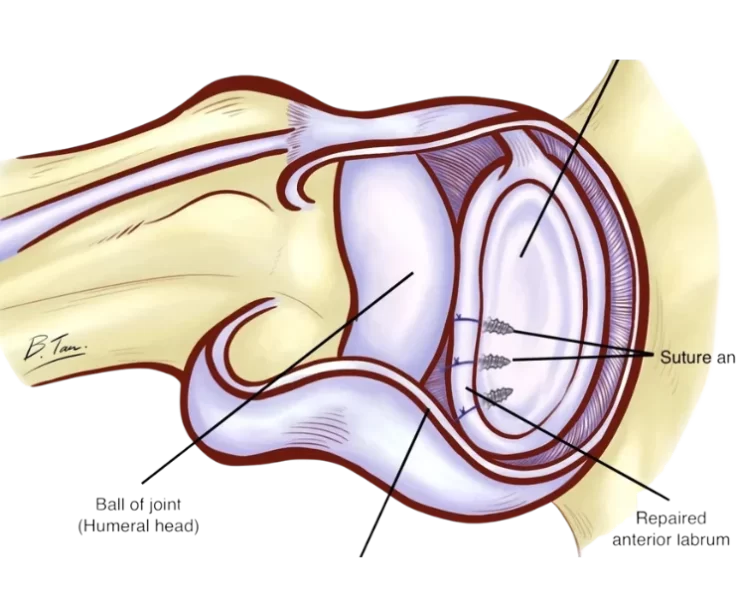

Bankart Repair

A Bankart Repair is a treatment that is used to avoid recurrent anterior shoulder dislocations caused by instability in the shoulder's rear.

SLAP Repair

The upper arm bone, shoulder blade, and collarbone make up your shoulder joint, which is a ball and socket joint.